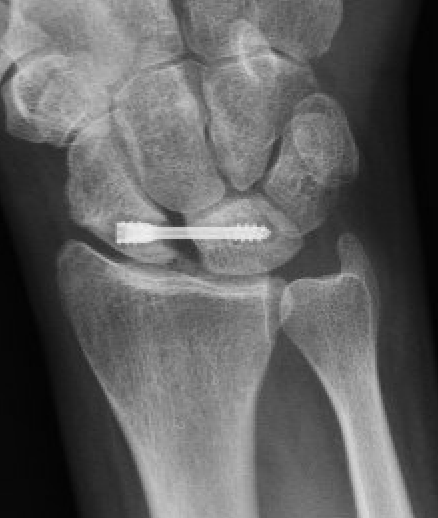

RASL (Reduction and Association ScaphoLunate)

Technique

Reduce SL joint with K wires

- secondary radial incision

- headless compression SL screw

- ? remove at 3 months

- creates mobile synchondrosis

Results

Aibinder et al J Wrist Surg 2018

- 12 patients with chronic SL injury treated with RASL

- 7 year follow up

- 7/12 developed degenerative changes

- 8/12 developed screw lucency requiring removal